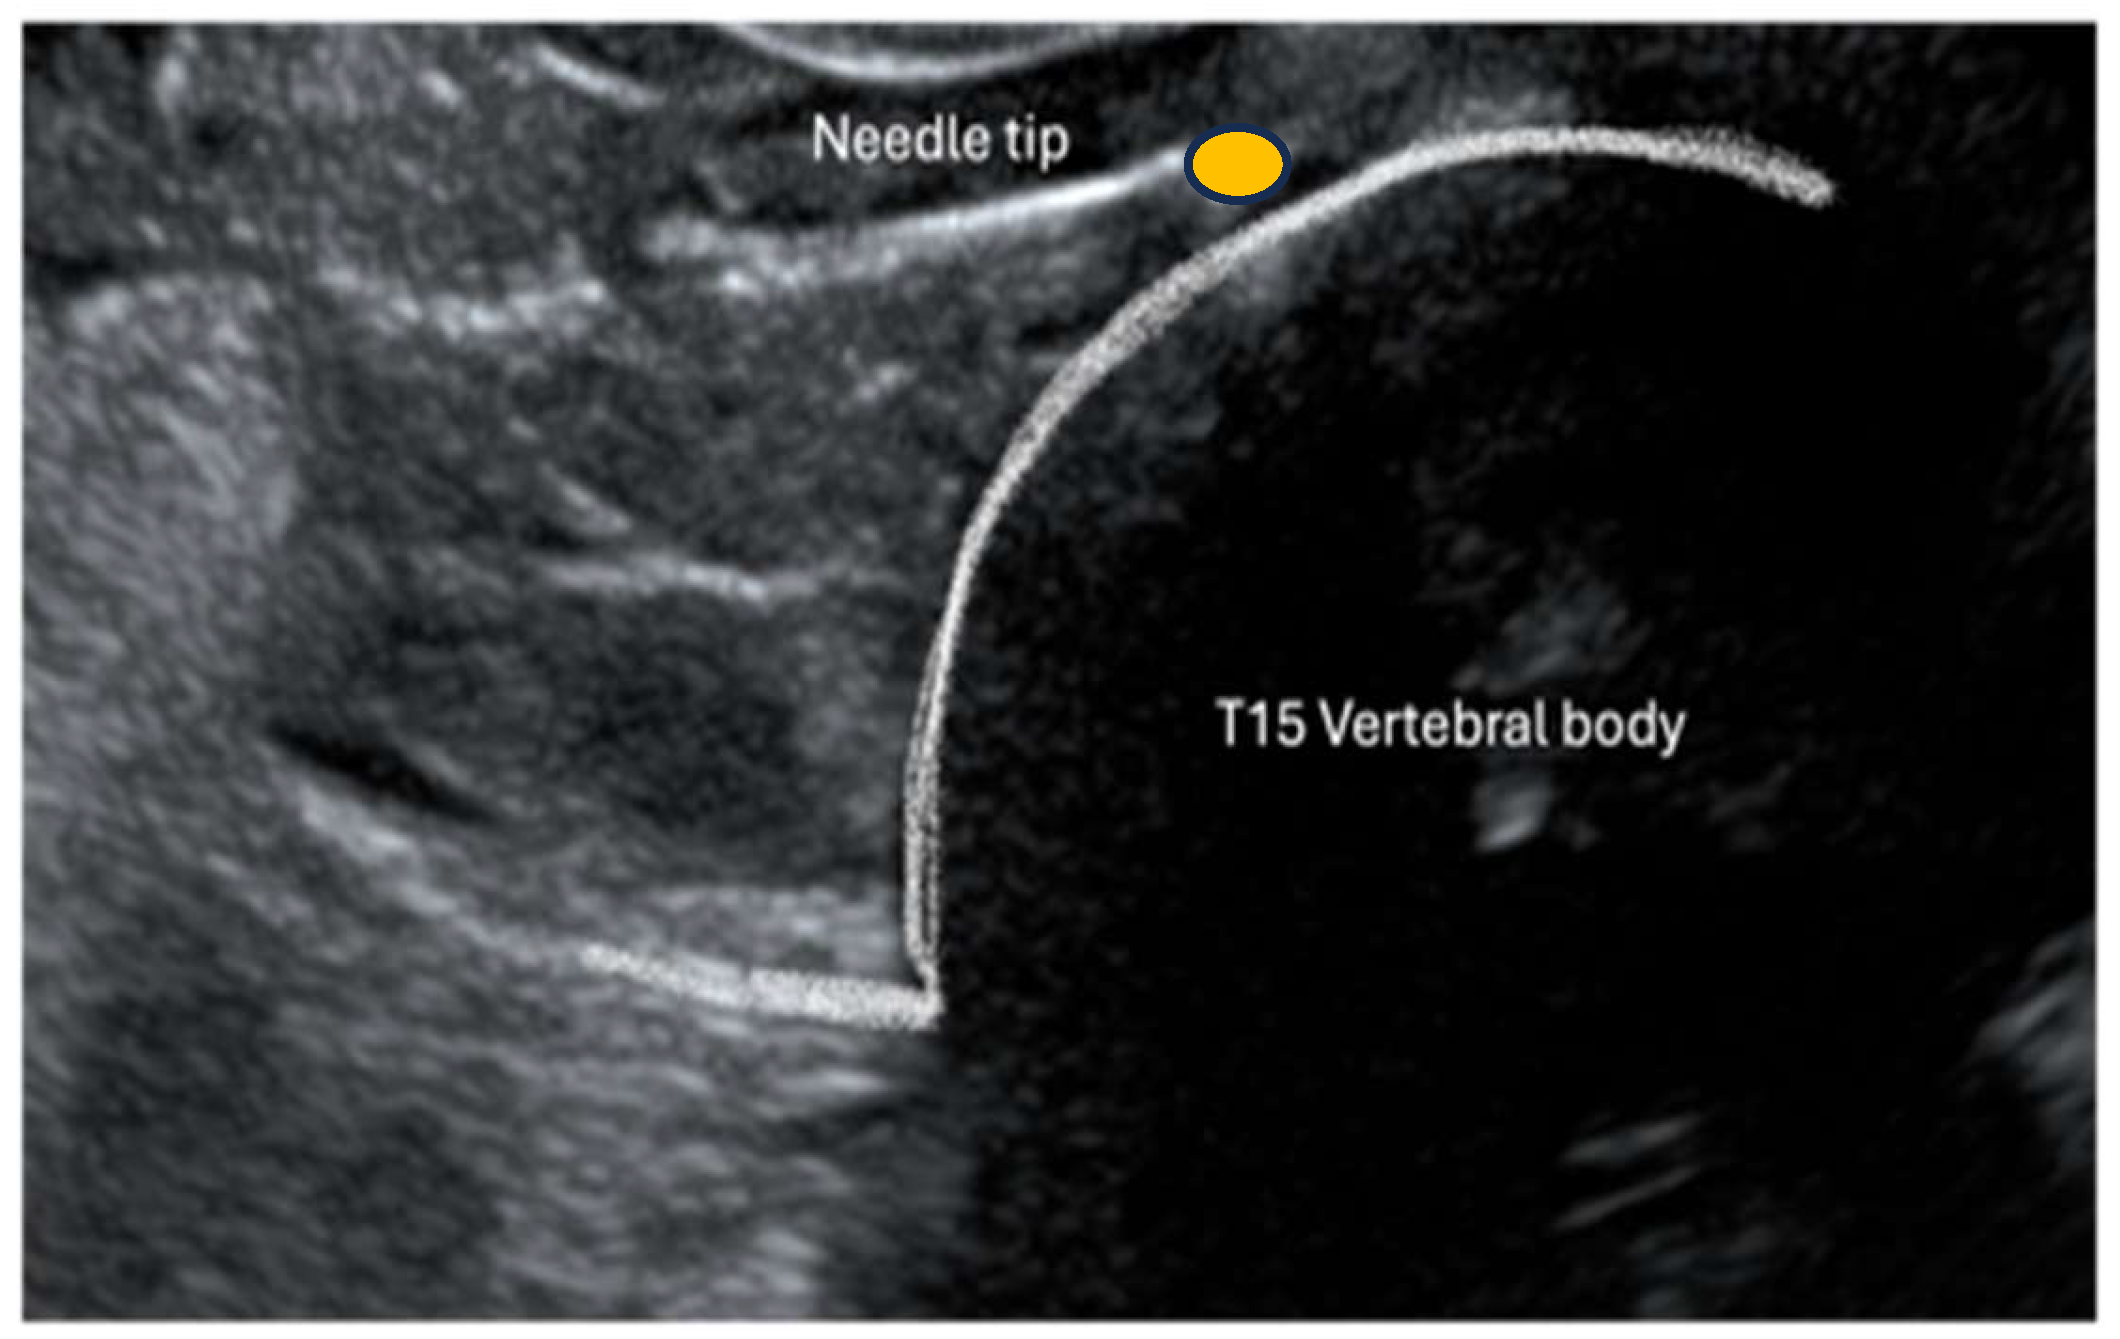

2.3. Ultrasound Approach to CP

3.1. Gross Anatomical Description and Ultrasonographic Technique